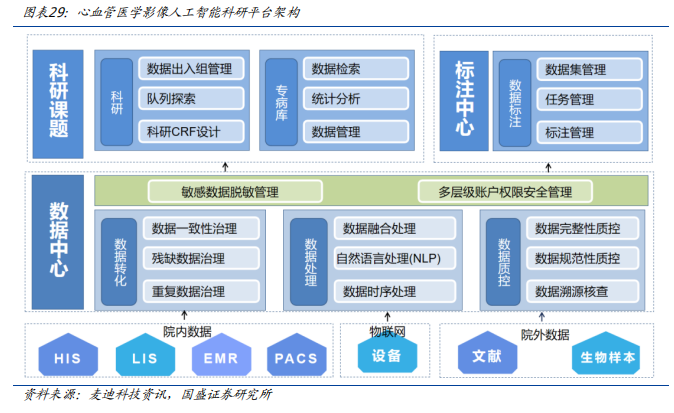

早在2023年,由麦迪科技研发的心血管医学影像人工智能科研平台在复旦大学附属中山医院落地。该项目是基于复旦大学附属中山医院在心血管疾病方向的学科集群优势,研发的一款与影像大数据库连接的“一站式”心血管医学影像人工智能科研平台,实现科研影像数据的快速收集,以及人工智能科研所需的标注、清洗、存储、训练和验证等功能。

心血管医学影像人工智能科研平台是基于计算机视觉网络模型的人工智能技术框架作为AI基础服务层,打造心血管人工智能影像分析平台为临床提供辅助诊疗服务。包含冠脉造影、血管内超声及CT血管造影等心血管疾病影像检测智能分析功能。通过对冠脉造影血管轮廓智能提取可以快速定位血管狭窄,完成血管狭窄分析,实现狭窄血管重建与定量测算,分析计算狭窄的功能学指标参数;同时还提供手术支架建议,便于快速制定介入手术方案。通过血管内超声影像分析可以快速完成血管内超声图像分析,实现斑块定位与测算,便于快速制定后续的治疗方案。